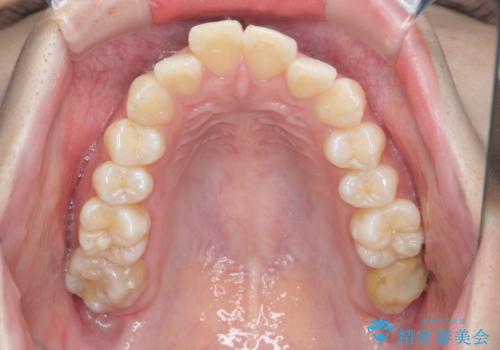

インビザラインで出っ歯の治療

- 「目立つ前歯の出っ歯をなんとかしてほしい。」と矯正治療を希望され来院されました。

突出した上顎の前歯に加え、ガタつきの目立つ下顎の歯列も同時にマウスピース矯正インビザラインで整えていきます。

突出間(所謂 出っ歯)のある前歯の位置は大幅に改善され、審美性が大きく向上しました。

加えて奥歯も噛み合わせも良くなったことで、咬合状態が安定しより安定した歯列を獲得することができました。